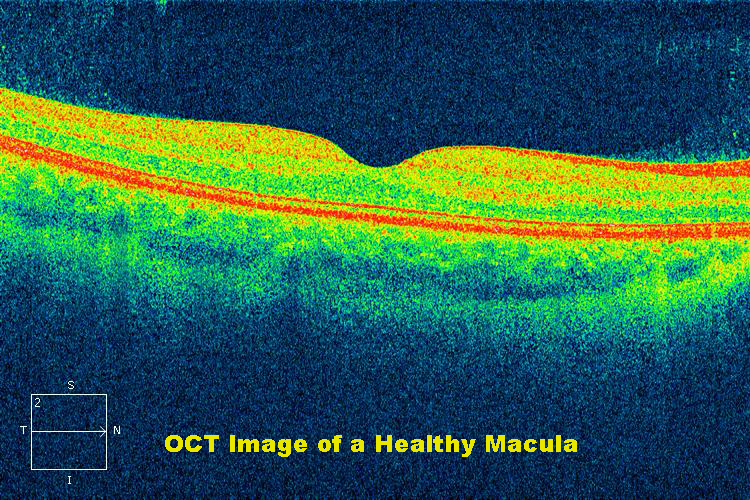

Диагностика зрения: Когерентная томография сетчатки